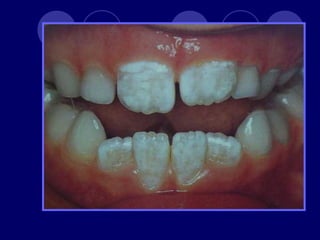

• 45.

AMELOGENESIS IMPERFECTA  Hipoplásico: Zonas ausentes de esmalte  Afecta más a caras vestibulares  Esmalte: blanco amarillento y marrón claro, consistencia dura, fosas y surcos oscuras, delgado  Hipocalcificado:  Cualitativo  Esmalte frágil, fácil de desprender  Rx: falta de contacto entre dentina, esmalte  Hipomaduro:  Disminución en el contenido mineral  Esmalte blando y rugoso, veteado de blanco a marrón (esmalte en copos de nieve)  Más frecuente en caras vestibulares y dientes superiores